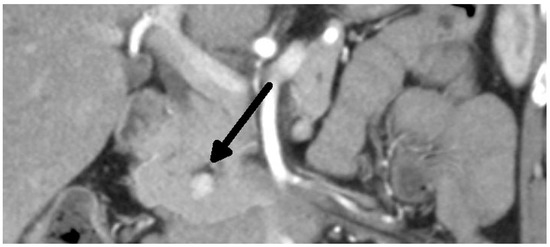

Overall, we performed a total of 116 scheduled surgeries on patients suffering from insulinoma. The surgically treated postoperative complications are listed separately. There were 79 females, with a mean age of 52 years (20–83 years, median was 51 years), and 37 males, with a mean age of 53 years (29–81 years, median was 59 years). The duration of the symptoms varied from 1 month to 25 years (mean was 3 years). All patients were examined in the 3rd Department of the Inner Medicine General University Hospital (which is focused on metabolic disease), including insulinoma localization. A fasting test was performed on all patients during hospitalization. Additionally, the levels of calcium and phosphates in the serum were examined in all patients, as well as in the hypophyseal region, to exclude MEN I syndrome. Radiological examination depends on the diagnosis period, and CT scan was used in all cases (Figure 1 and Figure 2). This was due to the unavailability of MRI, especially in the first years of the study.

Figure 1. Insulinoma—CT arterial phase (tumor marked with an arrow).